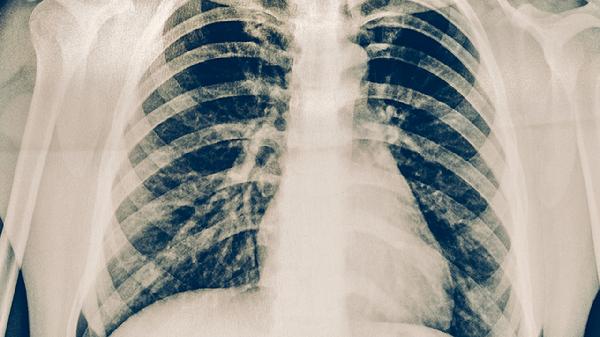

间质性肺炎如何康复 间质性肺炎的康复方法介绍

间质性肺炎可通过氧疗、药物治疗、肺康复训练、营养支持和心理干预等方式康复。间质性肺炎通常由环境因素、感染因素、药物因素、自身免疫疾病和遗传因素等原因引起。

间质性肺炎患者需建立规律作息,保证充足睡眠,避免过度劳累。注意防寒防暑,流感季节提前接种疫苗。保持居住环境通风良好,远离粉尘和刺激性气体。戒烟并避免二手烟暴露,适度进行温和运动如太极拳和散步。定期复查肺功能和胸部影像学,出现症状加重及时就医调整治疗方案。饮食上可多食用百合、梨子等润肺食材,避免辛辣刺激和油腻食物。